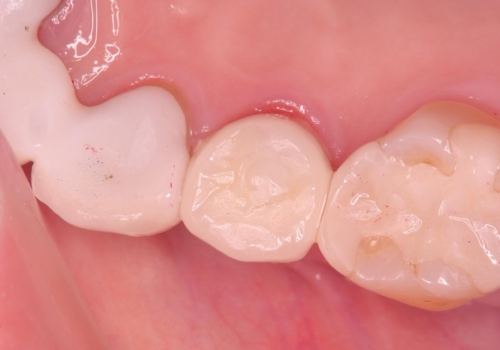

1日で抜歯、インプラント埋入、骨補填材を填入し仮歯【1DAYインプラント】までを数時間で行いました。

術後もほとんど痛みがなく経過も良好です。

3ヶ月後には、オールセラミック治療も終わり、短期間治療の為とても楽でしたと喜んでいただけました。